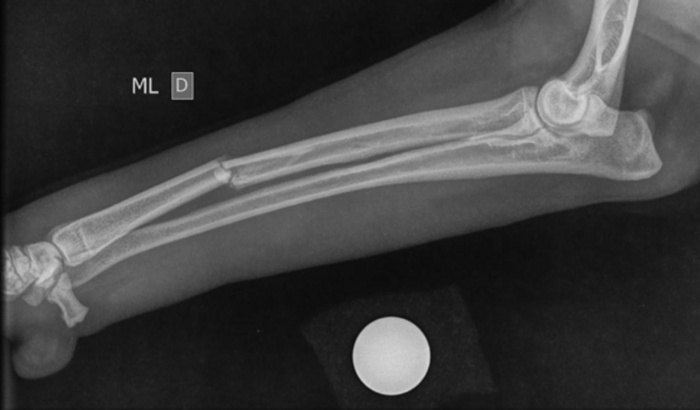

Oi Pessoal!!! O companheiro Labralata do meu pai foi atropelado aqui na Taquara essa semana, enquanto caminhava com meu pai na rua e teve uma fratura na patinha. Infelizmente precisará de cirurgia.